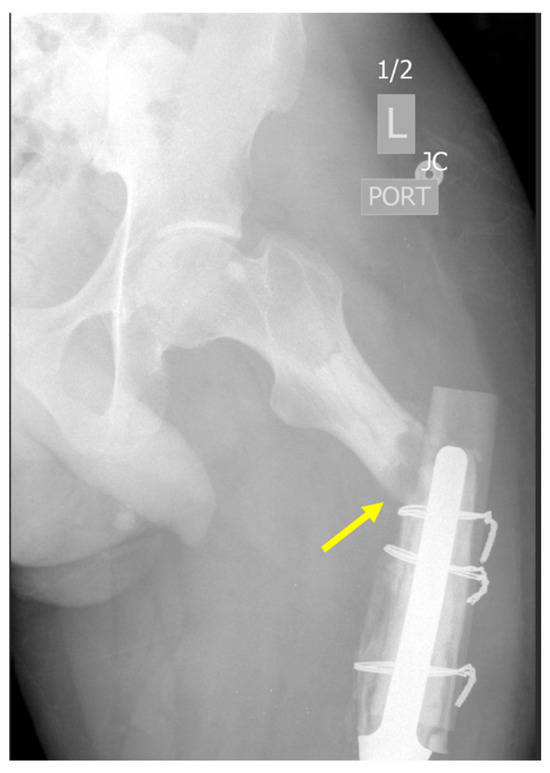

2.3.1. Structural Failure of Endoprostheses

- Type A: Fracture of an apophysis or protuberance of bone;

- Type B: Fracture involving the bed supporting or adjacent to an implant (B1, the implant is still well fixed; B2, the implant is loose; B3, the implant is loose and the bone bed is of poor quality);

- Type C: Fracture in the bone containing the implant but distant from the bed of the implant;

- Type D: Fracture affecting one bone which supports two replacements;

- Type E: Fracture involving two bones supporting one replacement;

- Type F: Fracture involving a joint surface which is not resurfaced or replaced but is directly articulating with an implant.